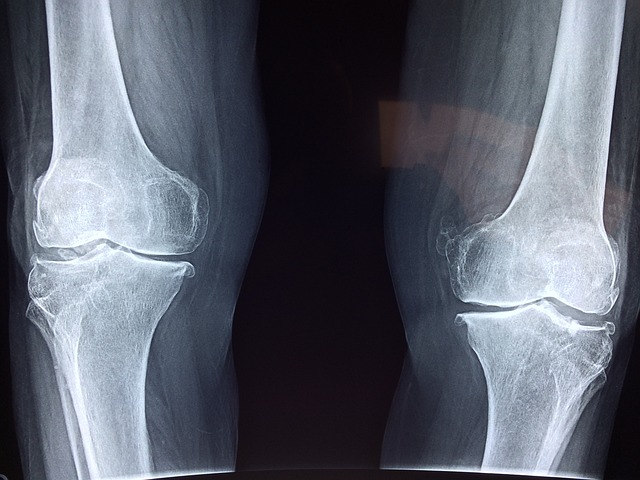

- 관절 통증 감소: 콘드로이친 효능으로 퇴행성 관절염 환자에게서 관절 통증을 줄이는 데 도움 됨이 있습니다. 이는 콘드로이친이 연골의 마모를 방지하고 염증을 줄이는 역할을 하기 때문입니다.

- 연골 보호 및 재생: 콘드로이친은 연골 세포의 생성을 촉진하고, 기존 연골을 보호하는 데 중요한 역할을 합니다. 이는 특히 나이가 들면서 발생하는 연골 손상을 예방하는 데 유용합니다.

- 염증 감소: 연구에 따르면 콘드로이친은 관절 내 염증을 감소시키는 데 효과적입니다. 이는 장기적으로 관절 건강을 유지하는 데 도움이 됩니다.

여러 연구에서 콘드로이친의 효능이 입증되었습니다. 예를 들어, 골관절염 환자를 대상으로 한 연구에서 콘드로이친이 관절 통증을 감소시키고, 연골 손상을 방지하는 효과가 있는 것으로 나타났습니다. 이러한 연구들은 콘드로이친의 장기적 사용이 안전하고 효과적임을 시사합니다.